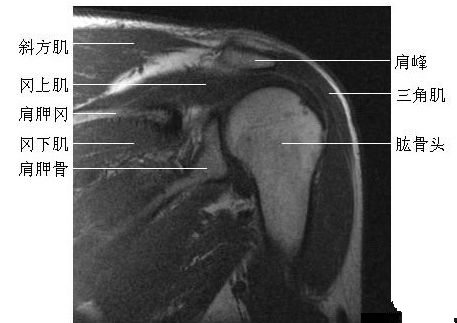

肩关节冠状面(一)